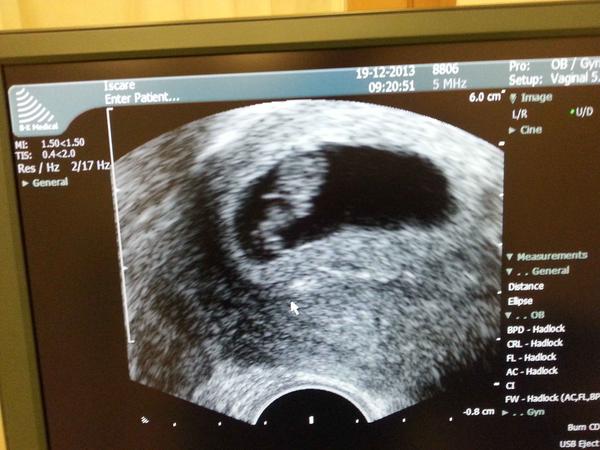

Aj ked sme napokon prekvapivo otehotneli spontanne, stale mam pocit, ze patrim do skupiny Iscare ...spoznala som tu super kocky, ktore nechcem len tak opustit a preto prikladam foto z dnesnej kontroly: 8tt. + 2d., 2 cm dlzka, srdiecko bije ako zvon ...